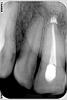

komar86 Опубликовано 29 августа, 2012 Поделиться Опубликовано 29 августа, 2012 Подскажите надо ли перелечивать два передних верхних зуба под протезирование? Что лучше на депульпированные пожелтелые зубы коронка безметаловая или винир? Ссылка на комментарий

DokDent Опубликовано 29 августа, 2012 Поделиться Опубликовано 29 августа, 2012 Подскажите надо ли перелечивать два передних верхних зуба под протезирование? Что лучше на депульпированные пожелтелые зубы коронка безметаловая или винир? Перелечивать надо Ссылка на комментарий